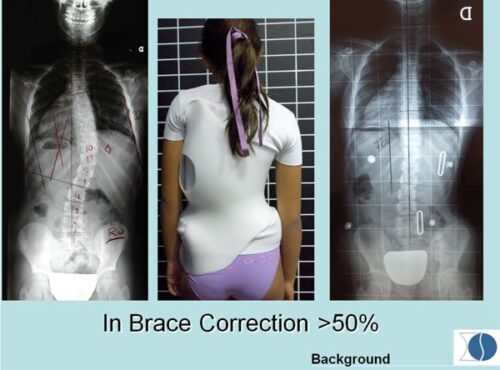

أجريت دراسة شملت 350 مراهقة مصابة بـ اعوجاج العمود الفقري. جميعهن استخدمن الحزام الطبي وتم متابعة النتائج على مدى فترة معينة. تم تصنيف المراهقات حسب وزن الجسم إلى مجموعتين: منخفضة الوزن وطبيعية الوزن أو أعلى.

حوالي 25% من المراهقات كن يعانين من نقص الوزن عند بداية العلاج، وانخفضت هذه النسبة إلى 13% عند المتابعة الأخيرة.

في مجموعة النجاح، كان معدل نقص الوزن 17.6%.

أما في مجموعة الفشل، فقد كان معدل نقص الوزن 43.1%.

التحليل الإحصائي أظهر أن انخفاض الوزن مرتبط بشكل كبير بفشل العلاج، مما يجعل وزن الجسم عاملاً مهمًا عند وصف حزام اعوجاج العمود الفقري.

التطور الكبير في تصميم الأحزمة الطبية جعل علاج اعوجاج العمود الفقري عند المراهقين أكثر نجاحًا وأقل إزعاجًا. باستخدام تقنيات التصوير الثلاثي الأبعاد والمحاكاة الرقمية، أصبح الحزام أكثر خفة وراحة، ويعطي نتائج أفضل في تصحيح الانحناء والتواء العمود الفقري.